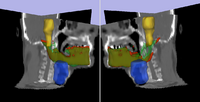

Adaptive Radiotherapy for Head, Neck and ThoraxWe proposed an algorithm to include prior knowledge in previously segmented anatomical structures to help in the segmentation of the next structure. This will add enough prior information to allow the Graph Cuts algorithm to segment structures with fuzzy boundaries. More... New: I. Kolesov, V. Mohan, G. Sharp and A. Tannenbaum. Coupled Segmentation for Anatomical Structures by Combining Shape and Relational Spatial Information. MTNS 2010.